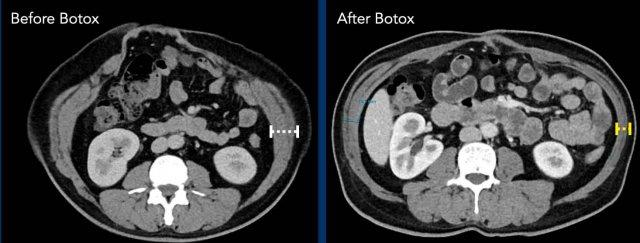

Hình ảnh

Hình ảnh các cơ chéo bụng bị mỏng và kéo dài sau khi tiêm Botox.